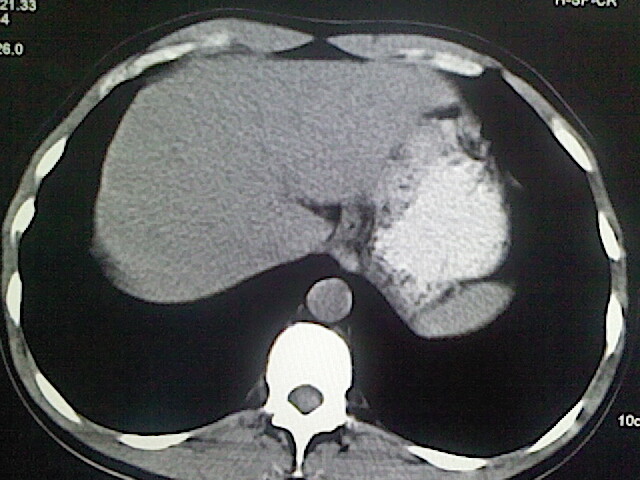

以下是引用卜一在2009-3-14 9:49:00的发言:[br]胆囊萎缩,胆囊壁不规则增厚,内部结构模糊,增强明显强化。另:肝左叶外侧段肝囊肿。支持:慢性胆囊炎!高度可疑:胆囊癌!

以下是引用余辉在2009-3-14 8:48:00的发言:[br]1)慢性胆囊炎。2)肝左叶外侧段肝囊肿。3)脂肪肝。[br]支持,胆囊萎缩,密度增高,不知b超具体有何提示,钙胆汁?结石?

以下是引用jiangjing在2009-3-14 10:18:00的发言:[br]1)慢性胆囊炎。2)肝左叶外侧段肝囊肿。3)脂肪肝。4.】建议行肝功能检查